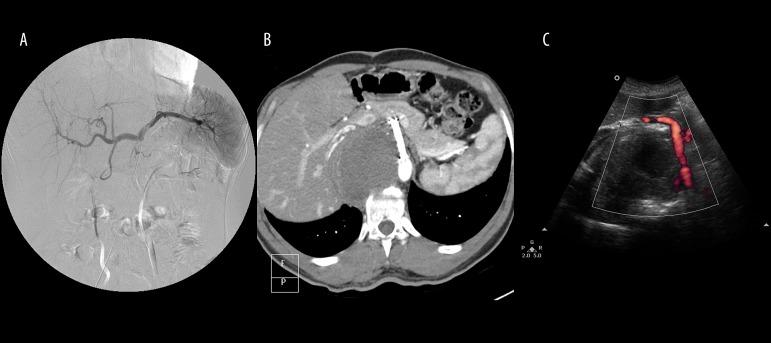

A 22-year-old man, who had undergone gastric, pancreatic and aortic surgery 2.5 years earlier, presented with progressive abdominal pain. Multidetector computed tomography scan revealed an 8-cm celiac pseudoaneurysm. We report a giant celiac pseudoaneurysm treated with stent-graft implantation.